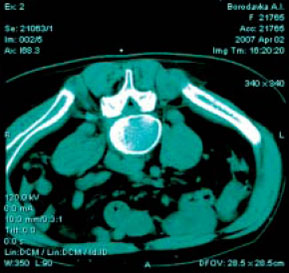

На рис.1 а,б представлены КТ в зоне L4-L5 до и после введения пункционной иглы. На рис.1 а,б представлены КТ в зоне L4-L5 до и после введения пункционной иглы.

С появлением методов визуализации, как, например, рентгеновской компьютерной томографии (КТ) данный вид воздействия принял «конкретные» очертания, давая возможность под визуальным контролем иглу для блокады подводить непосредственно к анатомической структуре, являющейся источником дорсопатии - перифуникулярному пространству в месте компрессии корешка. Этот вид воздействия получил названия малоинвазивной терапии и приносит ощутимый эффект непосредственно после проведения манипуляции, кумулируясь с каждым последующим введением лекарственного препарата и разрывая порочный круг боль – мышечный спазм – боль с выраженным патогенетическим воздействием на болевой синдром. Он широко и успешно применяется во многих странах дальнего и ближнего зарубежья в специально созданных Центрах боли. Методика прицельного введения лекарственных препаратов под контролем визуализации (в нашем случае КТ) врачам нашей клиники была любезно продемонстрирована Mario Wahler, врачом-нейрохирургом из г. Грейфсвальда (Германия), и мы имеем опыт ее положительного использования в нашей практике. На рис.1 а,б представлены КТ в зоне L4-L5 до и после введения пункционной иглы.

На рис.1 а,б представлены КТ в зоне L4-L5 до и после введения пункционной иглы.